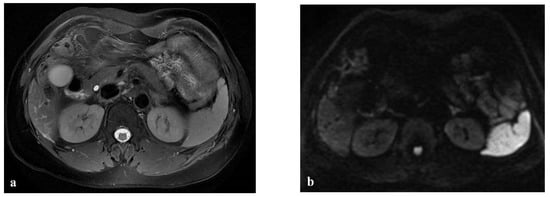

Another uncommon focal liver lesion that may arise in the spectrum of oxaliplatin-induced sinusoidal damage is hepatic peliosis. This condition is pathologically characterized by multiple or occasionally solitary mottled blood-filled cyst-like spaces in the liver with associated sinusoidal dilatation [4]. MRI findings of hepatic peliosis depend on the stages of the blood component in these lesions. In T1-weighted images after contrast material injection, peliotic lesions usually show typical centrifugal enhancement (from the center to the periphery of the lesion); in DW-MRI, peliosis is characterized by hyperintense areas with similar diffusion restrictions to hemangioma, while in the MRI HB phase, these lesions appear as hypointense areas because the blood-filled cavities lack functional hepatocytes (Figure 5). However, some lesions may show central enhancement, which is suggestive of a spared, normal hepatocyte area [42]. Liver biopsy is indicated in case of doubt to differentiate liver metastases from peliosis.

Figure 5.

(a–d) A 49-year-old man with hepatic metastases from colon cancer undergoing neo-adjuvant chemotherapy with folinic acid, 5-fluorouracil, oxaliplatin, and irinotecan (FOLFOXIRI) and with the association of bevacizumab. After chemotherapy, multiple small foci (arrow heads) appeared in the liver parenchyma, with the largest in segment 5 (arrow). This lesion was slightly hyperintense in the T2-weighted image (a) and presented slight restrictions in the DW-MRI image, with b-values of 1000 s/mm2 (b). The portal-venous phase (c) of the Gd-EOB-DTPA-enhanced MR image demonstrated inhomogeneous enhancement of the lesion, while in the hepatobiliary phase image (d), it appeared as a hypointense area. The biopsy of the largest lesion was diagnostic for peliosis.